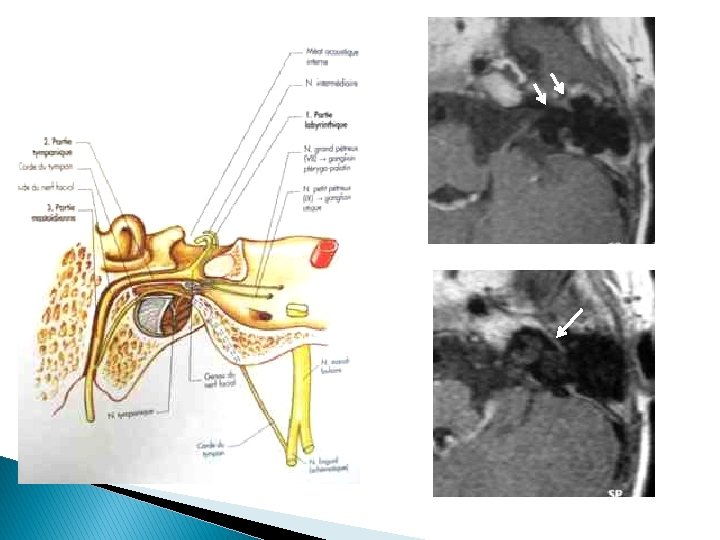

§ Prise de contraste physiologique : • Ganglion géniculé • Portion tympanique proximale : distribution des espaces périneuraux qui débutent après le ganglion géniculé vaisseaux périneuraux dépourvus de barrière hématoneurale

§ Jamais de PDC : • Segment intra-méatal distal • Segment intra-labyrinthique